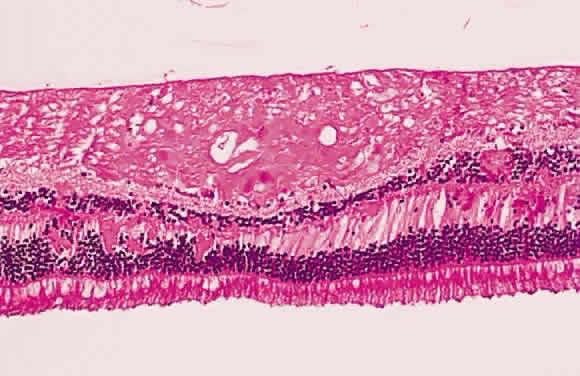

Fig. 19. Histologic section demonstrating response of the pigment epithelium to

injury. The sclera is at the bottom the micrograph; the choroid (c) contains scattered red blood cells and is edematous. The vitreous (v) also contains hemorrhage. Locate the pigment epithelium (short arrows) at the left third of the micrograph and notice the ribbons of pigment

epithelium that proliferate into the membrane, partially formed by fibrous

tissue (F). Bone (long arrow) also is present and probably was deposited by metaplastic pigment epithelium. Fig. 19. Histologic section demonstrating response of the pigment epithelium to

injury. The sclera is at the bottom the micrograph; the choroid (c) contains scattered red blood cells and is edematous. The vitreous (v) also contains hemorrhage. Locate the pigment epithelium (short arrows) at the left third of the micrograph and notice the ribbons of pigment

epithelium that proliferate into the membrane, partially formed by fibrous

tissue (F). Bone (long arrow) also is present and probably was deposited by metaplastic pigment epithelium.